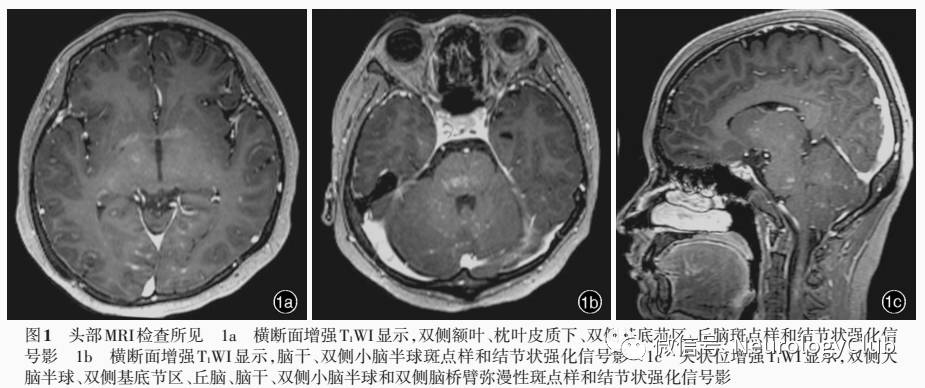

辅助检查  实验室检查:血常规白细胞计数0.80×10^9/L、中性粒细胞计数0.49×10^9/L[(2.00-7.50)×10^9/L],网织红细胞计数99.70×10^9/L[(24-84)×10^9/L]、网织红细胞比例0.0241,血红蛋白114g/L,血小板计数45×10^9/L,红细胞沉降率(ESR)2mm/h(0-20mm/h);血涂片:红细胞大小轻度不等,白细胞形态大致正常,血小板少见。血液化学总胆红素26.50μmol/L(5.10-22.20μmol/L),直接胆红素10.40μmol/L(0-6.80μmol/L),丙氨酸转氨酶(ALT)51U/L(7-40U/L),天冬氨酸转氨酶(AST)77U/L(13-35U/L),γ-谷氨酰转移酶(GGT)88U/L(7-45U/L),碱性磷酸酶(ALP)149U/L(35-100U/L),前白蛋白171mg/L(200-400mg/L),超敏C-反应蛋白(hs-CRP)0.64mg/L(0-3mg/L);外周血EB病毒DNA测定为4600拷贝/ml,EB病毒四项衣壳抗原IgG(VCA-IgG)呈阳性(6.97U/ml),衣壳抗原IgM(VCA-IgM)、衣壳抗原IgA(VCA-IgA)和早期抗原IgA(EA-IgA)阴性;免疫学指标水通道蛋白4(AQP4)及其特异性抗体NMO-IgG阴性,抗可溶性核抗原(ENA)抗体(4+7项)阴性;淋巴细胞亚群11项:(1)B淋巴细胞、自然杀伤T细胞(NKT)、CD4+T细胞和CD8+T细胞计数均显著减少,CD4+T细胞/CD8+T细胞比值增加。(2)纯真CD4+T细胞计数和比例显著减少。(3)CD4+T细胞第二信号受体(CD28)比例正常,CD8+T细胞第二信号受体(CD28)比例增加。(4)CD8+T细胞CD38比例增加。腹部超声检查显示,肝脏剑突下1.90cm、肋下未见,右肝斜径13.50cm,肝实质回声尚均匀,门静脉内径1.80cm;脾厚7.50cm、长径25.80cm、肋下8cm,脾门处脾静脉内径1.90cm,肠系膜上静脉内径1.80cm,提示脾大,门静脉系统扩张。甲状腺和颈部淋巴结超声未见明显肿大淋巴结,甲状腺左叶实性结节。胸部CT显示,双肺多发性结节影,双肺多发性淡片索条影,考虑感染性病变可能。骨髓细胞学检查(2016年10月28日),三系增生活跃,粒系比例55.5%,红系比例29.5%,粒红比例1.88∶1(1.00-5.20∶1),粒系各阶段细胞比例和形态大致正常,红系早幼红细胞和中幼红细胞比例增加、形态正常,红细胞形态正常,淋巴细胞与单核细胞比例和形态正常,骨髓涂片巨核细胞计数15个,均为颗粒巨核细胞,血小板计数减少。骨髓活检显示髂后少许骨和骨髓组织,骨髓组织中造血组织略减少,脂肪组织略增多,造血组织中粒红比例大致正常,巨核细胞可见。免疫组织化学染色,CD138、CD20、CD3和CD38呈散在阳性,CD15和髓过氧化物酶(MPO)呈阳性。腰椎穿刺脑脊液检查(2016年10月31日),外观清亮、透明,压力110mmH2O(1mmH2O=9.81×10^-3kPa,80-180mmH2O),细胞数为零,蛋白定量790mg/L(150-450mg/L),葡萄糖2.20mmol/L(2.50-4.50mmol/L),氯化物123mmol/L(120-132mmol/L),乳酸水平为1.75mmol/L;细胞学白细胞计数200个/0.50ml,激活淋巴细胞阳性,淋巴细胞比例0.90,提示轻度淋巴细胞反应;脑脊液EB病毒DNA测定1700拷贝/ml(<500拷贝/ml),EB病毒四项VCA-IgG阳性(3.83U/ml),VCA-IgM、VCA-IgA、EA-IgA呈阴性;寡克隆区带(OB)阴性。影像学检查:头部MRI显示,脑桥、双侧脑桥臂、双侧小脑半球、双侧额叶和右侧顶叶皮质下、双侧侧脑室旁、双侧侧脑室后角旁枕叶多发性斑点样和结节状异常信号影,考虑炎症性病变、脱髓鞘病变可能(图1)。颈胸椎MRI显示,C2-3、C5-7和T1-12水平髓内多发性异常信号影,增强扫描病变呈强化征象,考虑脱髓鞘病变可能(图2,3);颈椎生理曲度稍直。神经电生理学检查:肌电图(2016年11月4日)显示,体感诱发电位(VEP)正常,左侧脑干听觉诱发电位(BAEP)正常、右侧大致正常。